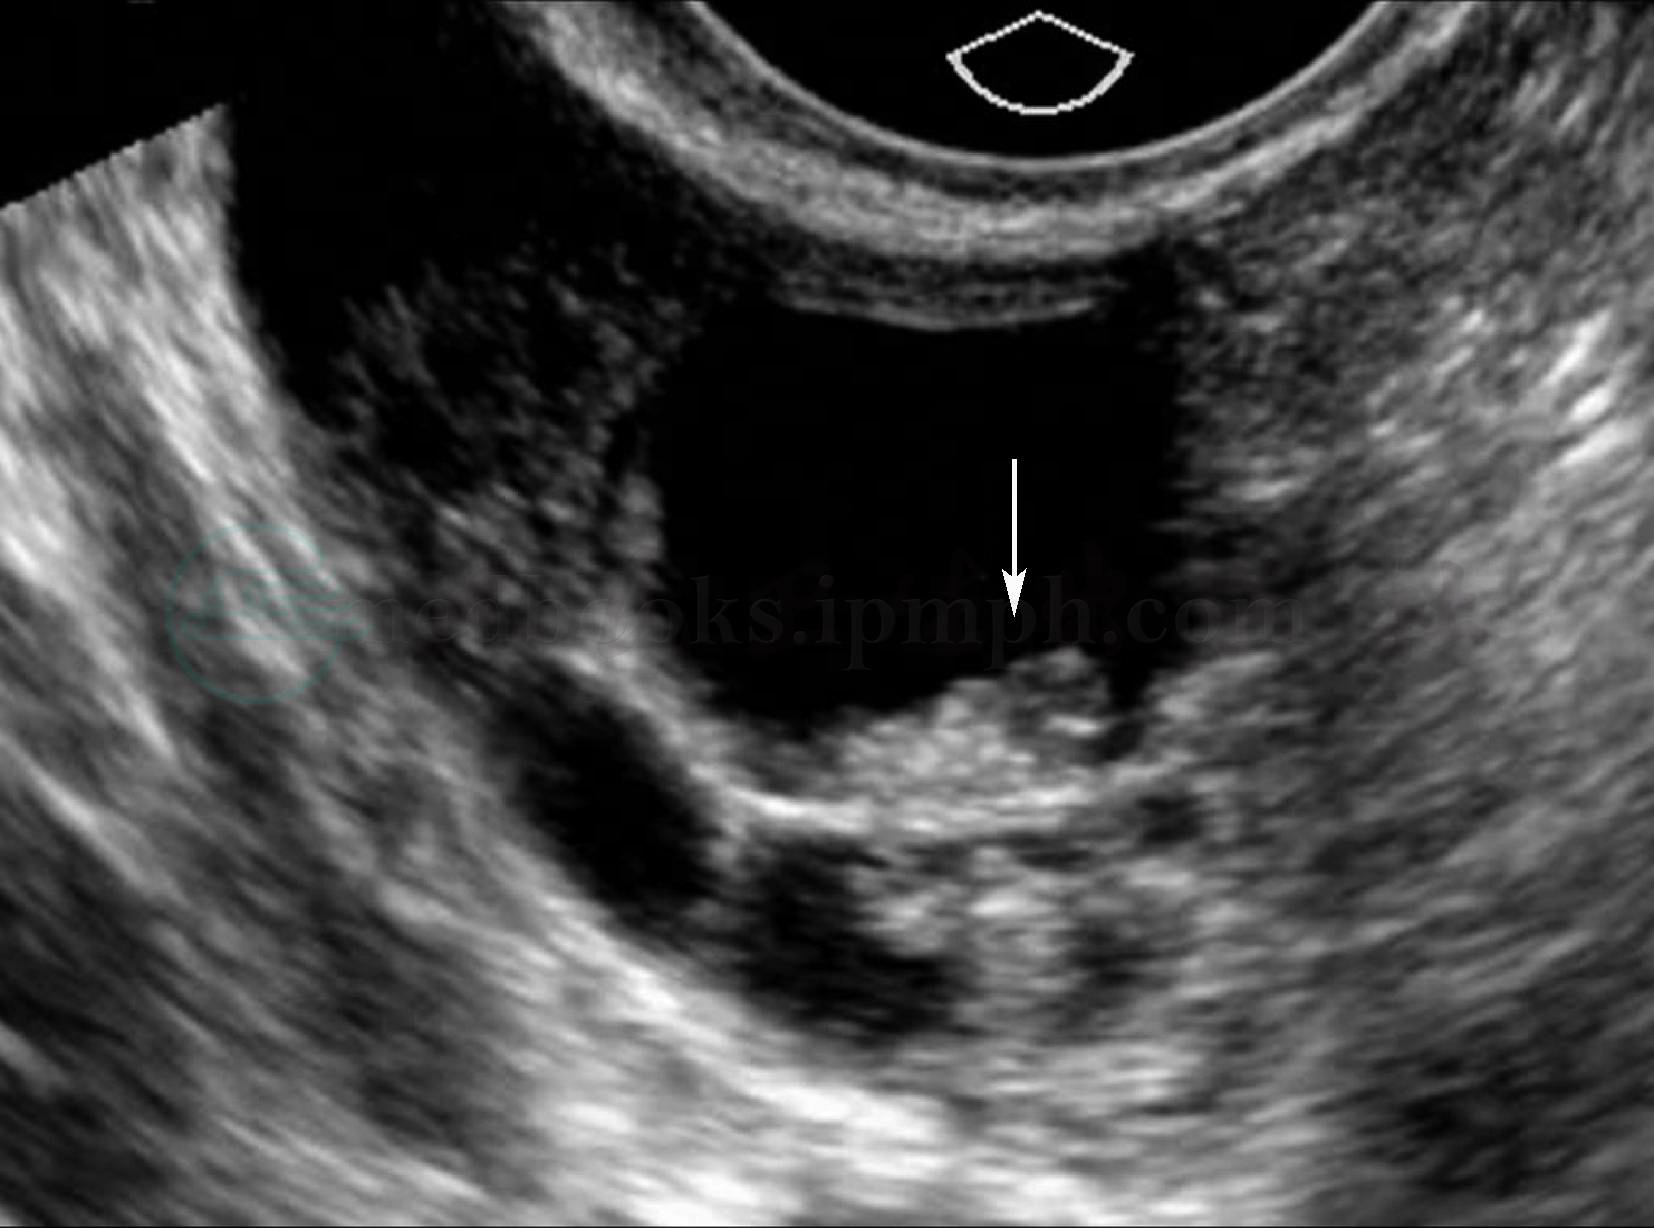

超声:中等大小,外形呈规则的类圆形,表面光滑,内部呈单房或多房囊性,分隔薄而规则,囊内透声好。浆液性乳头囊腺瘤囊内见单个或多个内生性和(或)外生性乳头,乳头形态较为规则(图1);CDFI 乳头内可见血流信号。少数病例发生于卵巢冠,仍可见部分正常卵巢组织的回声。

图1 卵巢浆液性乳头状囊腺瘤

卵巢内见无回声,内含网状分隔,隔上可见多个乳头样中高回声(箭头所指为乳头)